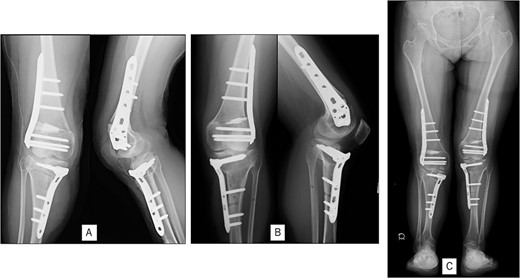

Postoperative radiography: (A) immediate postoperative radiograph of the right knee, (B) immediate postoperative radiograph of the left knee, (C) the entire lower limbs at 2 months after left knee surgery. Mild valgus deformity of the lower limbs persisted.

A 23-year-old woman presented with bilateral knee pain and gait abnormalities owing to marked lower extremity deformity. She was diagnosed with EVC as a child but had never been followed up by orthopedics because she was not in pain. On physical examination, marked valgus instability was observed in both knees, and the motion of both knees ranged from 10° to 135°. Radiographic examinations of both knees, including computed tomography, showed valgus deformity, lateral and anterior depression of the proximal lateral tibial plateau, and external rotation deformity of the lower leg. Patellar dislocation was observed in the right knee (Fig. 1). The radiological angles are presented in Table 1. The right knee underwent surgery first, followed by the left 10 months later. Lateral and medial skin incisions were made. Extensive lateral retinacular release, fractional lengthening of the distal lateral hamstring, and Z-lengthening of the iliotibial band were then performed. At this stage, peroneal nerve strain was identified, and decompression of the peroneal nerve was performed. Osteotomy was subsequently performed on the tibia. Closed-wedge varus and derotational osteotomy of the proximal tibia and open-wedge varus osteotomy of the distal femoral varus were performed. In addition, vastus medialis advancement was performed on the right knee, and patellar realignment was achieved in extension (Fig. 2). However, the knee showed a subluxation tendency owing to flexion of >30°; therefore, the postoperative rehabilitation plan progressed more slowly than that of the left knee. Range of motion training began on the left knee immediately after surgery without any restrictions, but on the right knee only after 3 weeks of postoperative immobilization in the extended position. However, ambulation exercise was performed on both knees with no loading for 3 weeks, then partial loading was initiated, and full loading was permitted at 8 weeks postoperatively. Early postoperative standing radiography showed residual mild valgus deformity of the lower limbs (Fig. 2, Table 2). In addition, the right knee showed patellar re-dislocation 2 months postoperatively, and the patellar deformity gradually progressed owing to the femoral implant; therefore, the patient underwent implant removal, tibial tubercle transfer, and medial patellofemoral ligament reconstruction 1.5 years after the initial surgery (Fig. 3). Six months later, she fell while walking and developed a fracture at the osteotomy of the right femur; open reduction and internal fixation were performed (Fig. 4). The remaining years passed uneventfully, and 10 years after the initial surgery, the patient still had mild valgus deformity of the lower limbs, but had no recurrence other than that experienced immediately after surgery, no complaints of knee pain, and a stable gait (Fig. 5, Table 2).